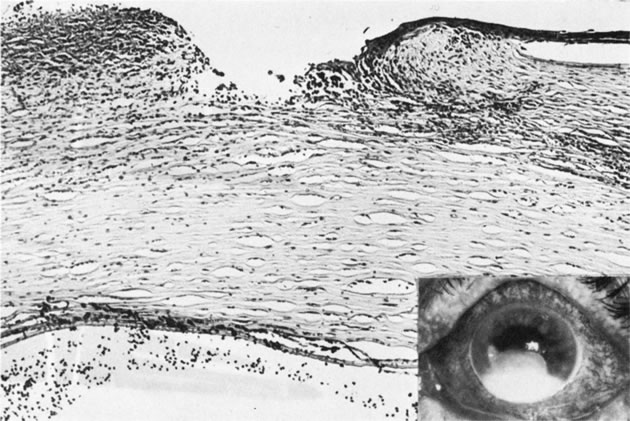

Reis-Bucklers' Dystrophy (Corneal Dystrophy of Bowman Type I [CDB-I])

Reis-Bucklers' dystrophy, also called anterior limiting membrane dystrophy, is a primary abnormality of Bowman's membrane, resulting in replacement of the native membrane with layers of abnormal collagenous tissue.135 This autosomal dominant disease is expressed clinically in early childhood by painful recurrent erosions. The episodes continue to occur through the first and second decades of life and then become quiescent, only to recur in the fifth and sixth decades. Following multiple episodes, the abnormal Bowman's membrane is seen as a subepithelial translucent layer with diffuse corneal scarring (CDB-I) and a honeycomb pattern (Thiel Behnke corneal dystrophy—CDB-II) due to the deposition of abnormal collagen.136

Loss of hemidesmosomes of the basal squamous epithelium can be seen with electron microscopy in early cases. An abnormal material composed of peculiar “curly filaments” is produced at the basal lamina of the epithelial cells in CDB-II.137 In more advanced cases, Bowman's membrane appears by light microscopy to be focally digested, a pattern similar to that seen in corneal stromal dystrophies, which are associated with recurrent erosion. Bowman's membrane ultimately may be replaced completely by reparative collagenous tissue. The corneal stroma in CDB-I and CDB-II are normal (Figs. 27 and 28). Electron microscopy of CDB I reveals granular type opacities.CDB I has been localized to chromosome 5q31 and CDB II to chromosome 10q23-q24.138,139 Streeten has shown that both the granular or rod-shaped deposits in Reis-Bucklers' dystrophy and the “curly fibers” of Thiel-Behnke dystrophy are immunoreactive for BIGH3 protein, consistent with mutations in the BIGH3 gene.140

Fig. 27. Reis-Bucklers'dystrophy (corneal dystrophy of Bowman type II [CDB-II]). A. Early stage shows small, white dots in continuity with the band of relucency representing Bowman's membrane. Biopsy (inset) is oriented to correspond to drawing. Bowman's membrane (b) is destroyed at the top. B. Moderately advanced stage shows confluence of the whitish subepithelial mounds in the characteristic honeycombed pattern. C. The abundant subepithelial tissue composed of peculiar curly filaments is highly characteristic of the entity. The filaments are closely interwoven, with regions of thin basement membrane. Hemidesmosomes along the epithelial basal cell (EP) are fewer than normal. The basilar cell processes are abnormal. Inset shows degeneration of Bowman's membrane in several foci (arrows indicate membrane remnants). The thick, avascular, fibrous membrane present under the epithelium forms mounds that produce a typical honeycombed pattern in three dimensions. (Courtesy of SEI Photoarchives.) (A modified from Griffith DG, Fine BS: Light and electron microscopic observations in a superficial corneal dystrophy: Probable early Reis-Buckler's type. Am J Ophthalmol 63:1659, 1967; B and C modified from Perry HD, Fine BS, Caldwell DR: Reis-Buckler's dystrophy: A study of eight cases. Arch Ophthalmol 97:664, 1979.)

Fig. 28. Reis-Bucklers' dystrophy. A. Late-stage Reis-Bucklers' dystrophy. B. Bowman's membrane (arrow) has degenerated, and a heavy subepithelial pannus has formed. The remainder of the stroma is normal. Inset shows high magnification of the area where Bowman's membrane has been destroyed. (Courtesy of SEI Photoarchives.)